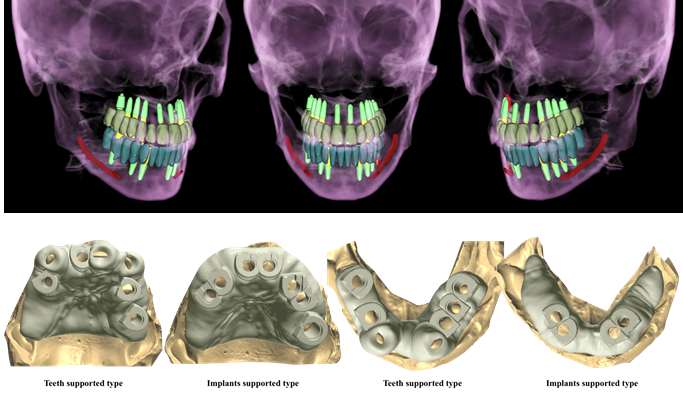

Effective R2STUDIO in complex tooth positioning

- Courtesy of Dr. Jong Cheol Kim, Korea